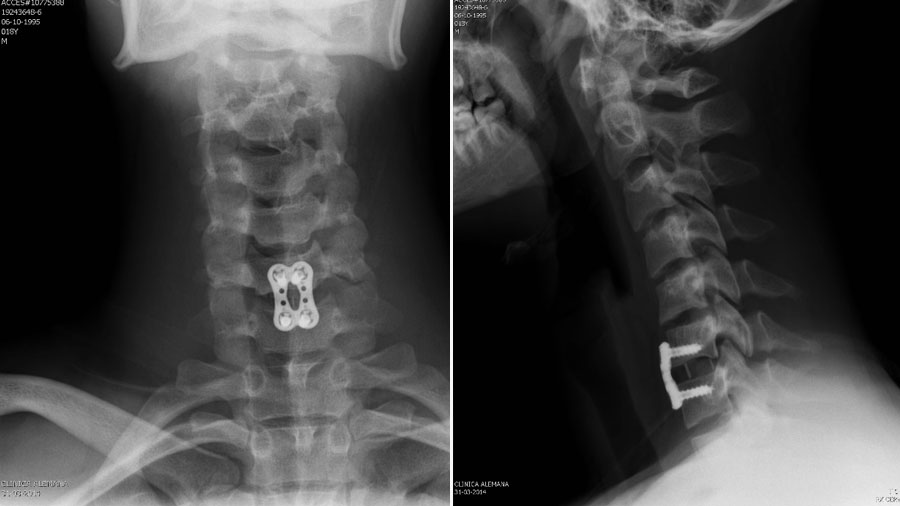

Management: The patient underwent an anterior cervical discectomy and fusion (ACDF) at C6–C7 with anterior plating. The approach showed a complete rupture of the disc. The postoperative recovery was uneventful, and the symptoms resolved.